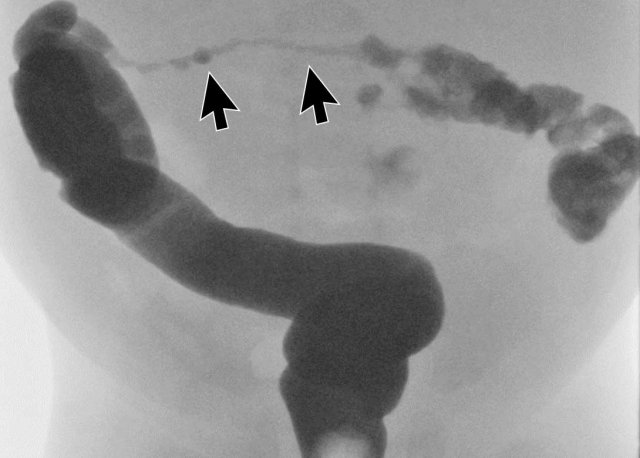

Image

Colonic stricture after NEC (arrows).